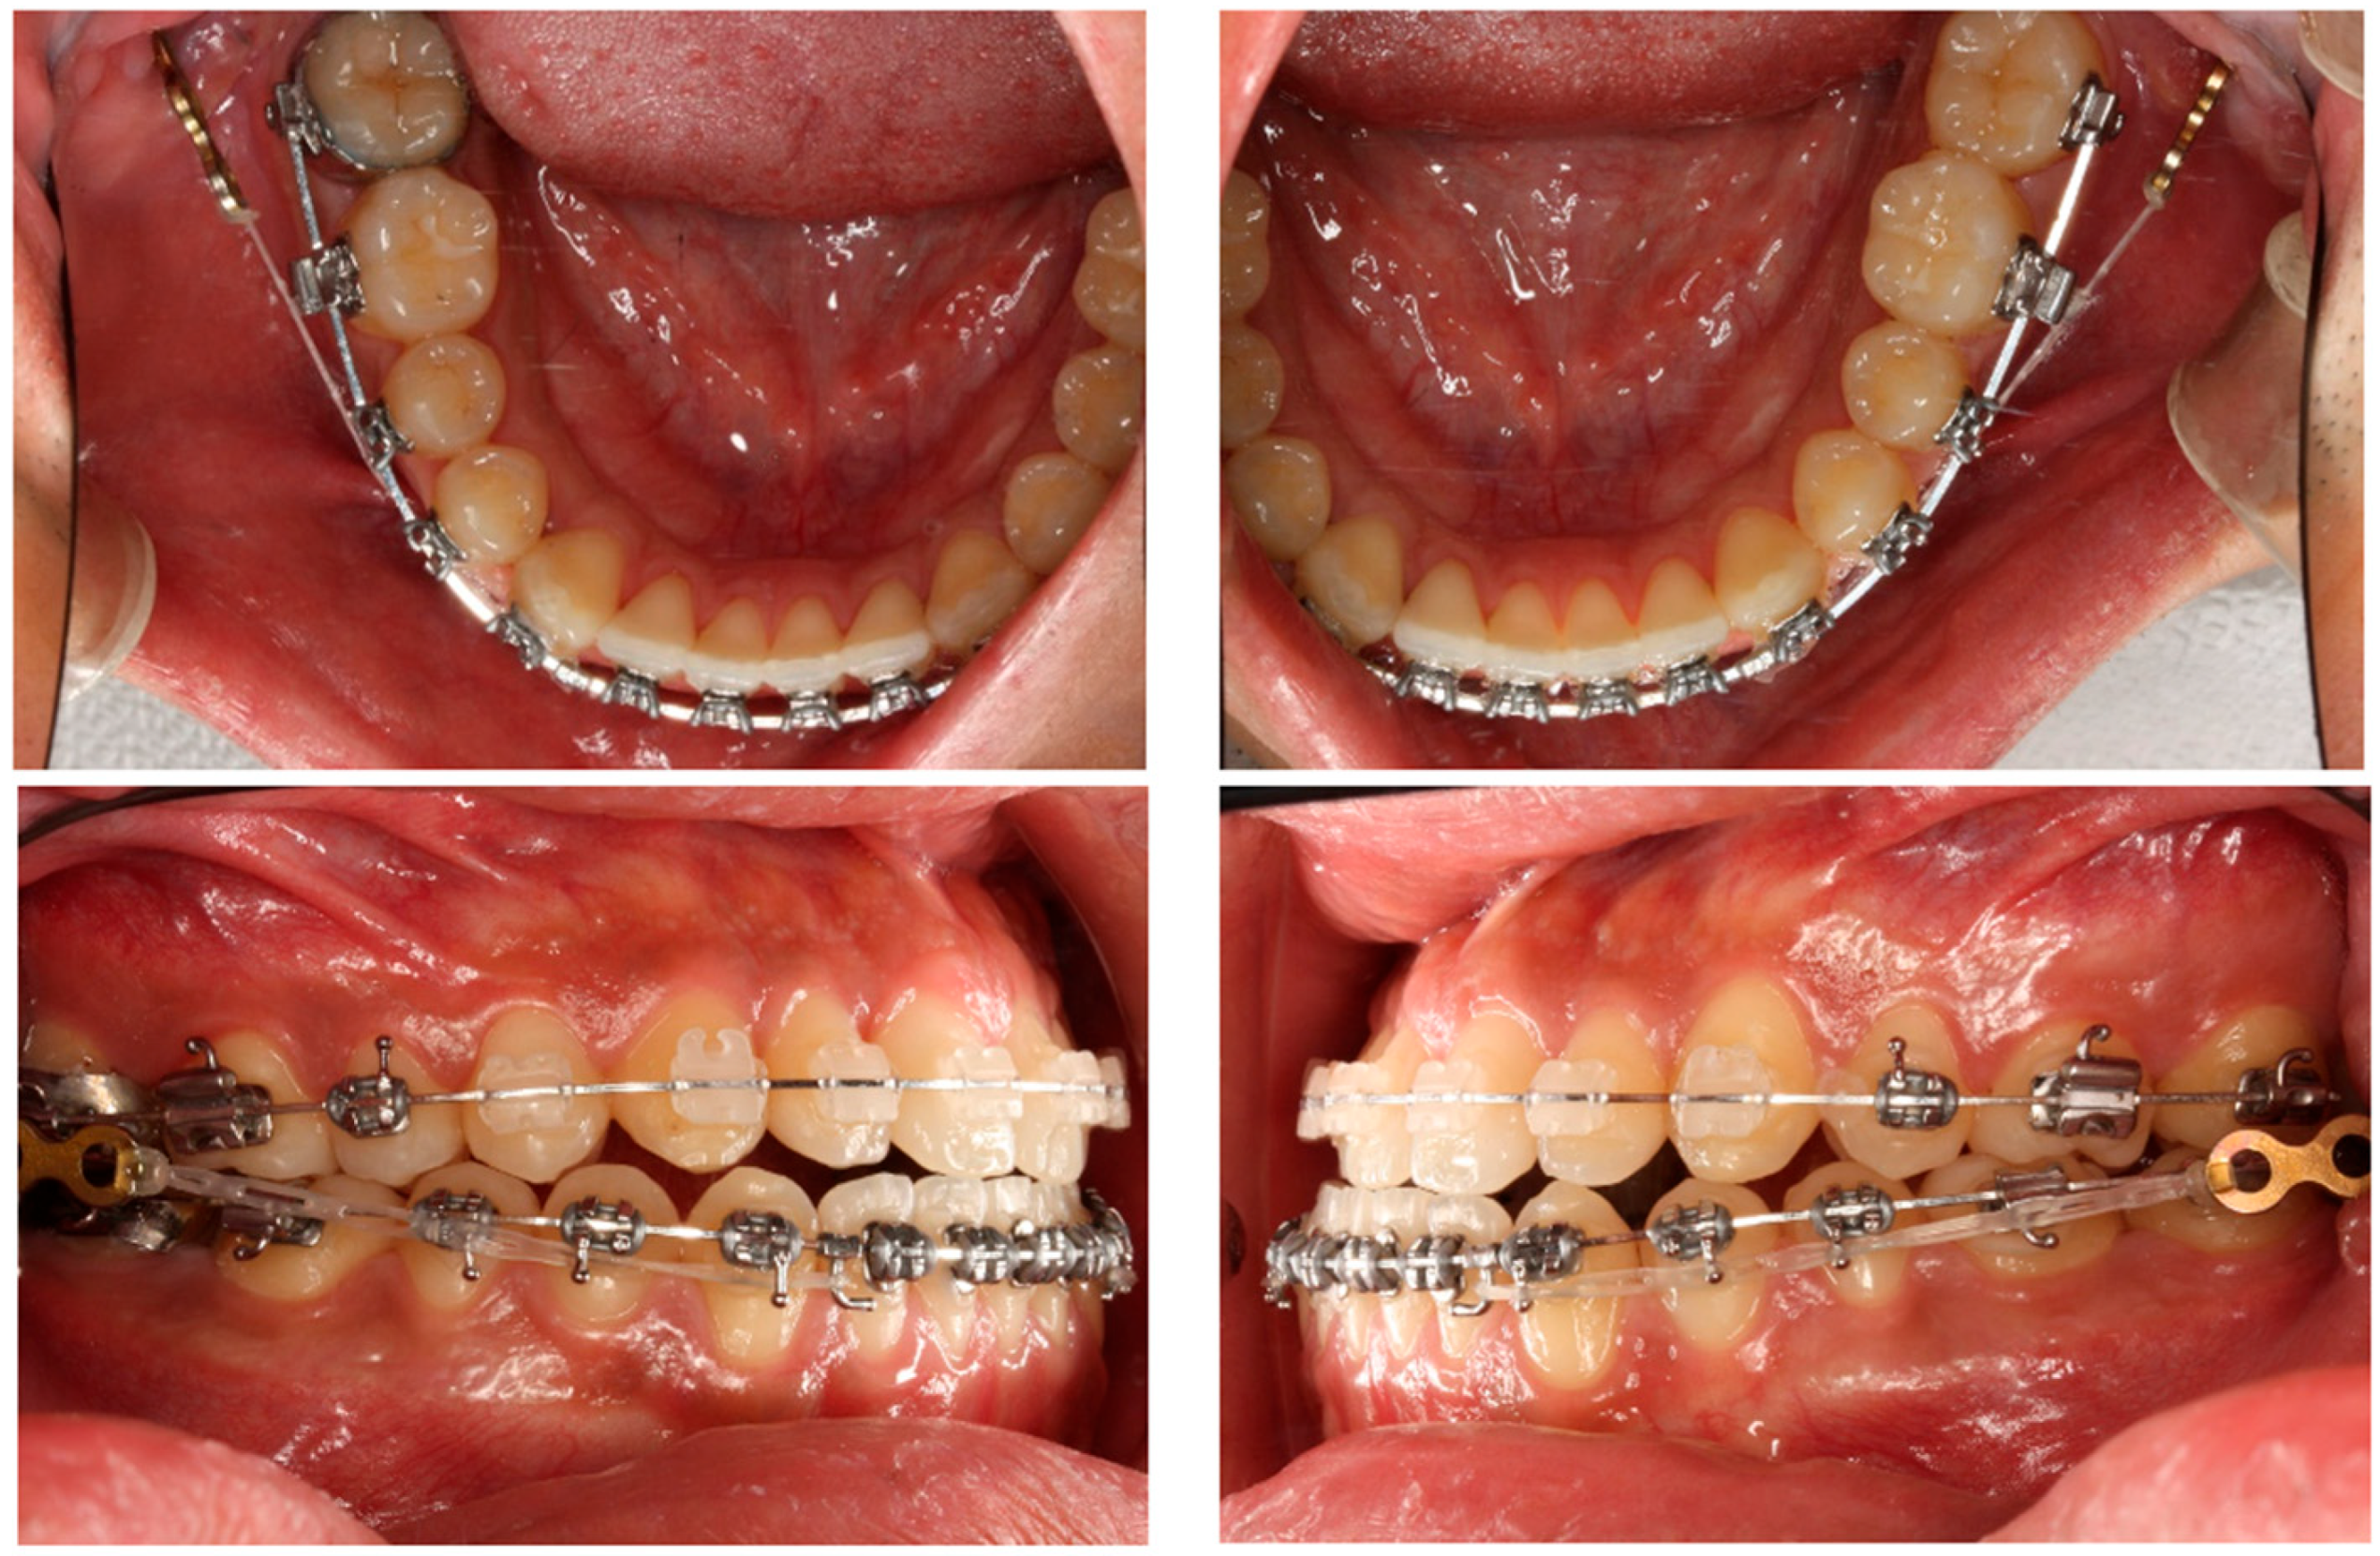

2.1. Treatment Progress